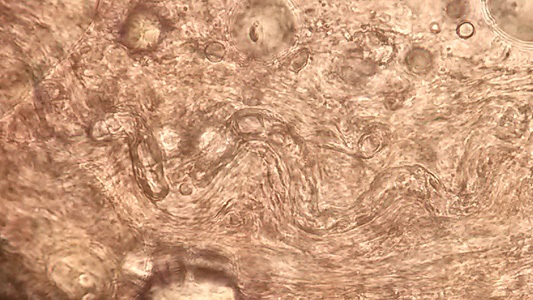

A 55 year old man from Tasmania, Australia presented with progressive general muscle weakness and myositis with 27 lb weight loss and loss of muscle mass for over two years. The patient was a keen hunter and liked to cook and eat the game he killed. He had little travel history, having previously lived in North Queensland, but no other part of Australia. A previous muscle biopsy found only chronic myopathy with inflammatory infiltrates and fibrosis. He had an elevated eosinophil count and was treated with prednisone for assumed autoimmune myositis. His condition deteriorated to the point where he was admitted to intensive care. In hospital, his serum creatine kinase (CK) was 2130 U/L, alanine aminotransferase (ALT) was 51 U/L, C-reactive protein (CRP) was 39 mg/L and erythrocyte sedimentation rate (ESR) was 45 mm/hr. The patient’s eosinophil count was 1.3 × 109/L. A second muscle biopsy was taken, and a squash prep revealed a nematode (length ~350 µm), and several were seen in cross-section of a histological section of skeletal muscle, in which the diameter could be measured (20-25 µm).

Figure A. Muscle squash preparation image courtesy of Ms. Belinda McEwan Microbiology Department, The Royal Hobart Hospital.

Figure A